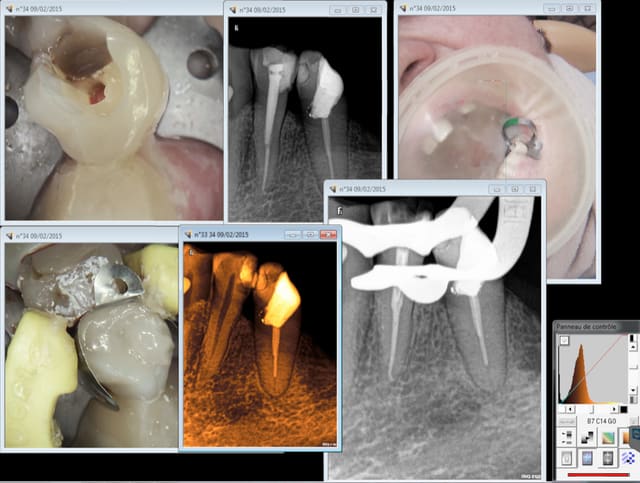

> > Patiente venue me voir en septembre 2011, après avoir été charcuté par un

> > dentiste qui ne maitrisait visiblement pas la cavité d'accès (lime cassée et

> > perforation monstrueuse)... et s'être vu proposé un implant par deux autres

> > dentistes.

Dans le cas présent, il n'y a pas de trop grande différence de rétention entre l'inlay-core dans son logement (racine mésiale généralement frêle), la couronne par dessus avec un effet ferrule réduit, et l'inlay collé sur la dent adjacente (j'ai juste fait une boite en mésiale et approfondi la cavité occlusale pré existante).

De plus, je fais systématiquement des bridges provisoires pour "tester" mes reconstructions, et en attendant la cicatrisation... Et là, le bridge provisoire a tenu plus de deux mois, scellé avec du temp bond sans eugenol. J'en déduis que la reconstruction sera durable dans le temps.

En tout cas là, au bout de 3 ans, c'était impeccable. Pas de récession, pas de bourrage alimentaire, pas de douleur et parfaitement scellé.

Dans le pire des cas, si la racine se fracture ou si le bridge venait à se desceller avec une reprise de carie, il sera toujours temps de faire un implant. Mais honnêtement, je n'y crois pas, je n'ai jamais eu d’échec de la sorte, pour la simple et bonne raison que je réfléchi tout le temps au principe biomécanique de mes reconstruction, et que je les éprouve à l'aide de mes provisoire. Bien sûre, je n'applique pas les mêmes tarifs que Chicot... Je ne descend jamais en dessous de 850 pour l'IC+couronne, et la plupart du temps c'est plus autour de 950, voir 1050-1100 lorsqu'il s'agit de céramo-céramique.

Pour carident, une image qui donnerait l'air d’être une perforation lors de l'ouverture.

Avec en plus des mesiaux bien rétractés et les limes qui souhaitent aller plus dans la carie qu'à l’intérieur des canaux.